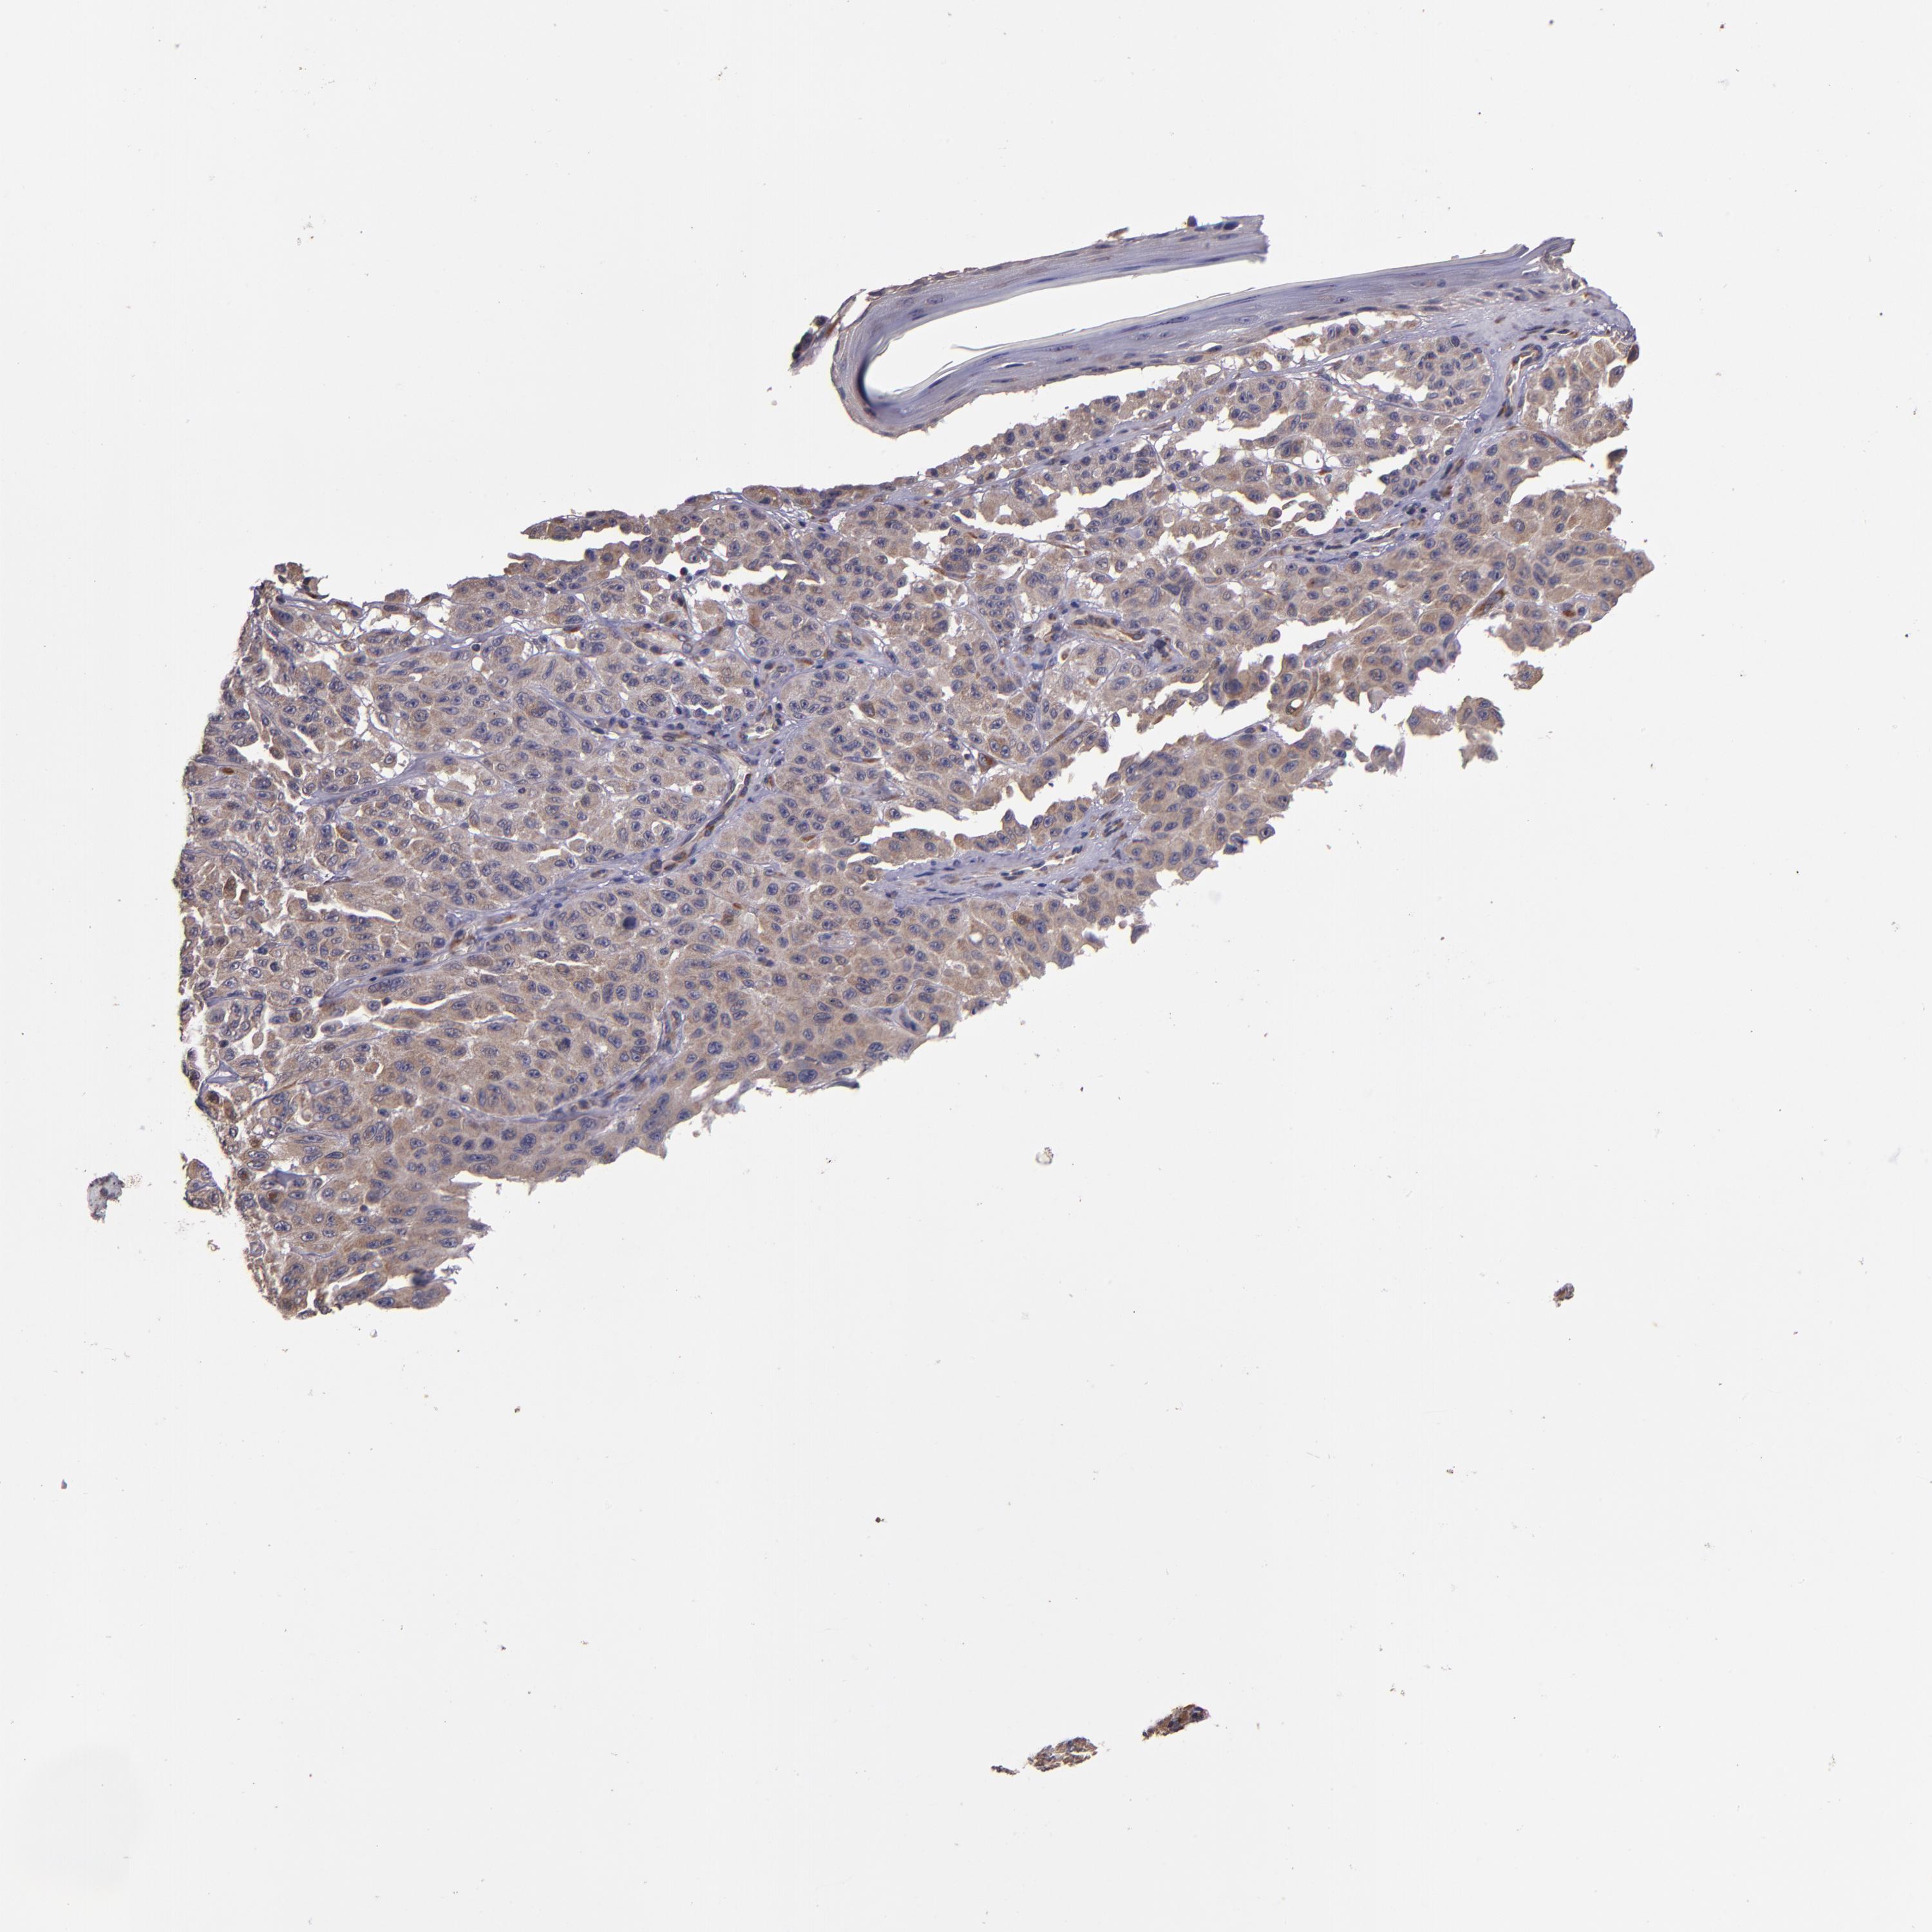

MELANOMA - Protein expressioni

A mouse-over function shows sample information and annotation data. Click on an image to view it in a full screen mode. Samples can be filtered based on level of antibody staining by selecting one or several of the following categories: high, medium, low and not detected. The assay and annotation is described here.

Note that samples used for immunohistochemistry by the Human Protein Atlas do not correspond to samples in the TCGA dataset.

Antibody stainingi

Antibody staining in the annotated cell types in the current human tissue is reported as not detected, low, medium, or high, based on conventional immunohistochemistry profiling in selected tissues. This score is based on the combination of the staining intensity and fraction of stained cells.

Each image is clickable and will lead to virtual microscopy that enables deeper exploration of all samples and also displays staining intensity scores, fraction scores and subcellular localization as well as patient and tissue information for each sample.

Antibody HPA002859

Antibody CAB011655

Staining

High

Medium

Low

Not detected

Intensity

Strong

Moderate

Weak

Negative

Quantity

>75%

75%-25%

<25%

None

Location

Nuclear

Cytoplasmic/membranous

Cytoplasmic/membranous,nuclear

Malignant melanoma, NOS

Malignant melanoma, Metastatic site